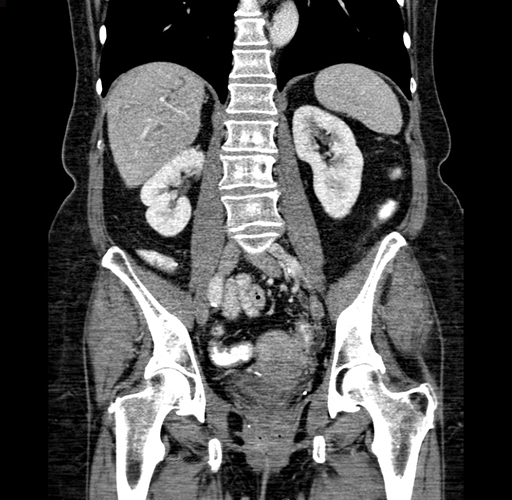

Pre-Chemo: Coronal Venous

Coronal Venous